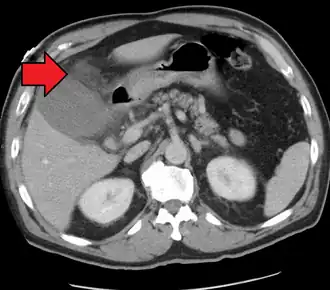

![]() Acute cholecystitis as seen on CT. Note the fat stranding around the enlarged gallbladder. | |